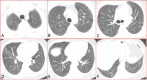

In pulmonary medicine, identical pathogenesis due to varied etiological agents can present with indistinguishable clinical presentation, and produce similar laboratory and radiological changes. The importance of eliciting detailed occupational and social history from patients cannot be stressed enough when dealing with patients suffering from diffuse parenchymal lung diseases. Hot Tub Lung(HTL) is a perplexing pulmonary disease attributed to the Mycobacterium Avium-intracellulare Complex (MAC). MAC is a ubiquitous atypical mycobacterium present in moist environment, and is not considered pathogenic, without the predisposing conditions like immunosuppression. However, HTL is a unique disease seen in healthy individuals following the exposure to contaminated hot water in spas. The less virulent MAC will, in healthy individual will elicit mild granulomatous inflammation particularly around the peribronchiolar region, which leads to the development of diffuse parenchymal lung. We report a case of HTL to increase the awareness of this rare and enigmatic disease among medical professionals, and to reiterate the importance of eliciting social and occupational details in clinical practice.